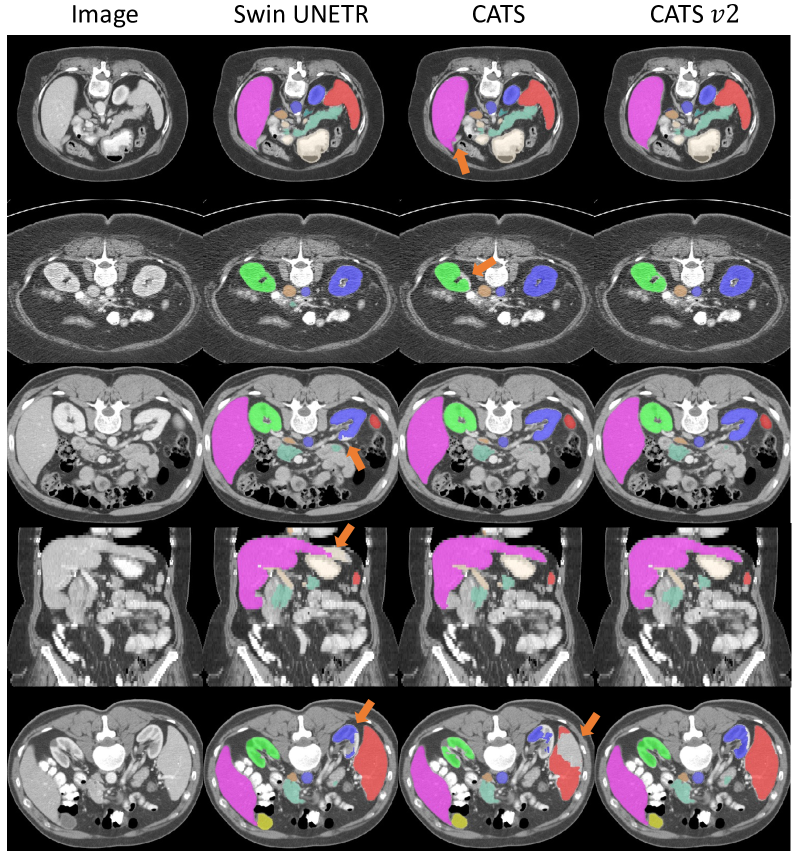

The quantitative and qualitative results of BTCV dataset are shown in Tab. 1 and Fig. 2, respectively. The compared methods include TransUNet [12], UNETR [13], Swin UNETR [15], CATS [20], and the proposed CATS v2. Briefly, UNETR [13] is composed of a ViT encoder and a CNN decoder, while Swin UNETR replaces the ViT with a Swin encoder. Similarly, CATS [20] is built upon the 3D U-Net [27] and integrates a ViT encoder. The proposed CATS v2 employs a Swin encoder as the upgrade.

From Tab. 1, the proposed CATS v2 achieves the best overall performance among the state-of-the-art compared methods (the ‘Avg.’ column). In the comparison between Swin UNETR and proposed CATS v2, we observe the improvements in 8 out of 13 organs when a CNN encoder is integrated. Furthermore, the proposed CATS v2 outperforms original CATS in 7 out of 13 organs, with larger improvements observed in organs of smaller volume, such as the gallbladder, and the right and left adrenal glands. These improvements suggest that the Swin encoder could further refine the local details. Fig. 2 shows qualitative results, with major differences highlighted by orange arrows. Compared to the Swin UNETR and the original CATS, our proposed model produces smoother results.